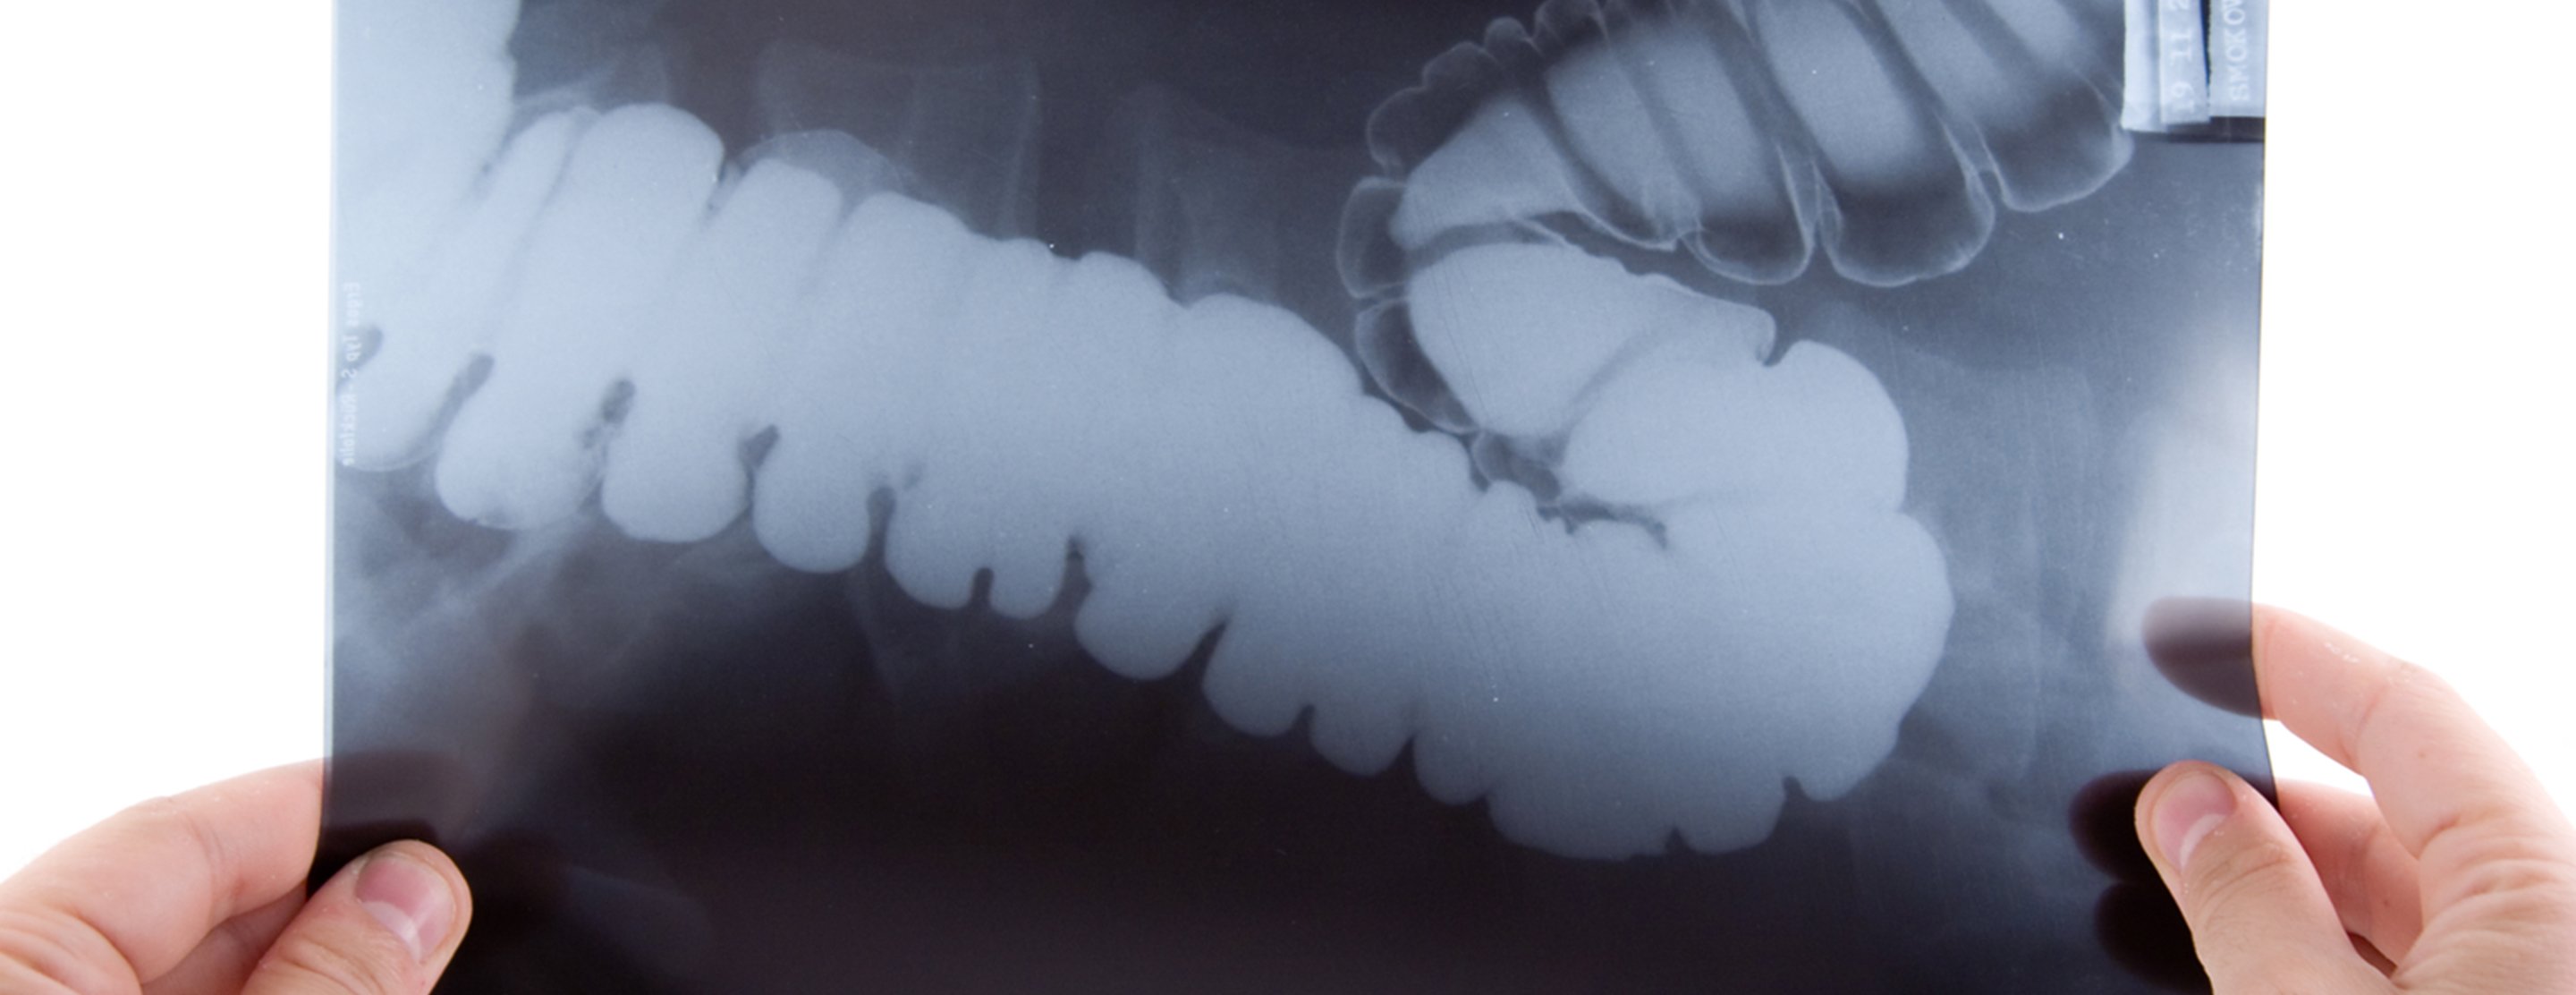

Abdominal x-ray

An abdominal x-ray is an imaging test to look at organs and structures in the abdomen. Organs include the liver, spleen, stomach, and intestines.

When the test is done to look at the bladder and kidney structures, it is called a KUB (kidneys, ureters, bladder) x-ray.